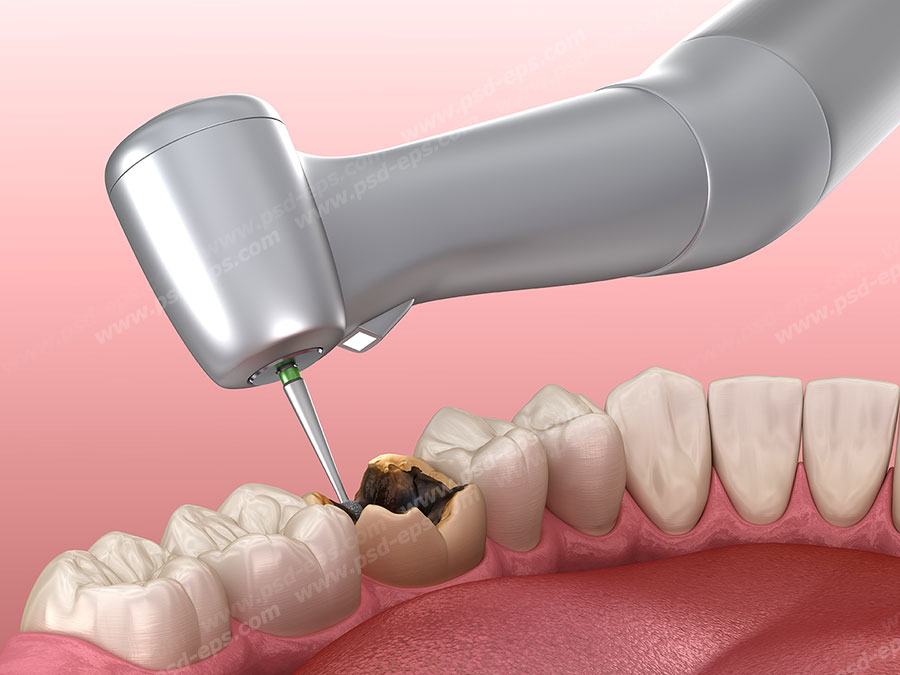

محفظة داخل دندان که حاوی رگهای خونی و عصب ها است پالپ نام دارد. خوردن بیش از حد در عارضه پرخوری عصبی باعث افزایش پوسیدگی دندان ها می شود اسیدهای قوی که در اثر استفراغ کردن از دهان خارج می شوند می توانند دندان ها را ضعیف و شکننده کنند این اسیدها همچنین باعث بوی بد دهان می. کشیدن دندان شیری رویش دندان شیری ریزش دندان شیری خراب شدن دندان شیری ریختن دندان شیری دندان شیری تعداد دندان شیری دندان شیری کودکان. من سی سالمه و اکثر دندان هام خراب شده یکی رو کشیدم دو تا رو پر کردم و دو تای دیگه رو هم دکتر گفت باید پر کنم و نیاز به عصب کشی دارند.

مهم ترین کار یک معاینه ی کامل است این معاینه شامل نگاه سطحی بر دندان های شما گرفتن عکس با استفاده از اشعه x از آنها و ساختن مدل پلاستیکی از دندانهای شما میشود سپس تیم دندانپزشکی یا. عکس بیت کوین به زودی وارد مبادلات مالی می شود. تشخیص پوسیدگی دندان ها از روی عکس های رادیو گرافی کاری است که نیاز به علم مربوطه دارد.